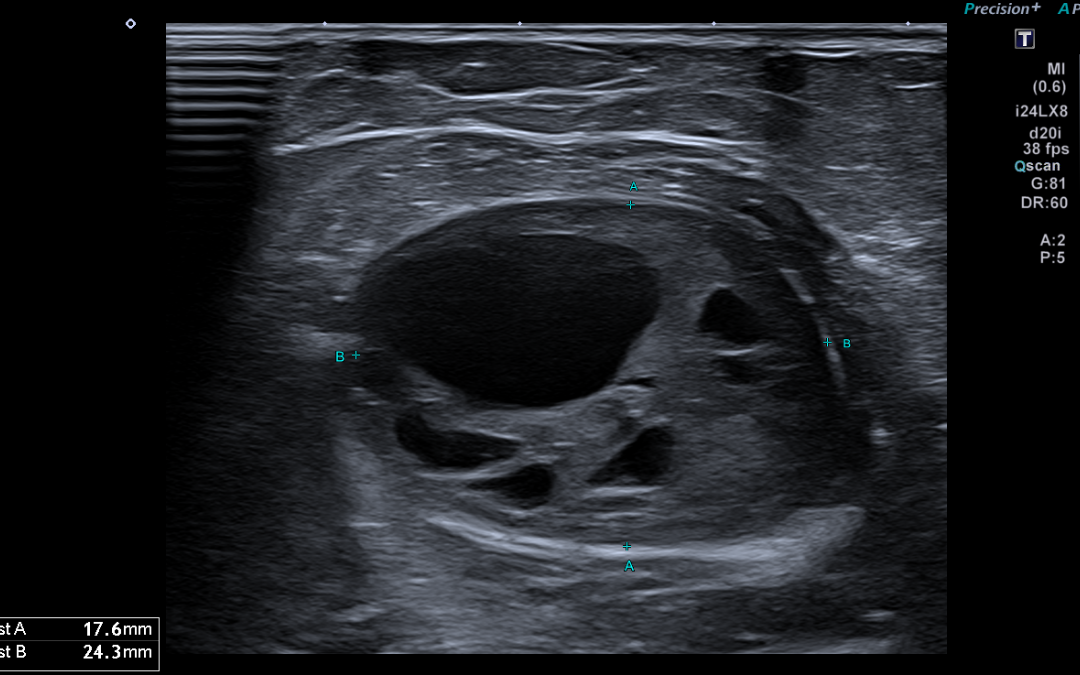

Hallazgos radiológicos: